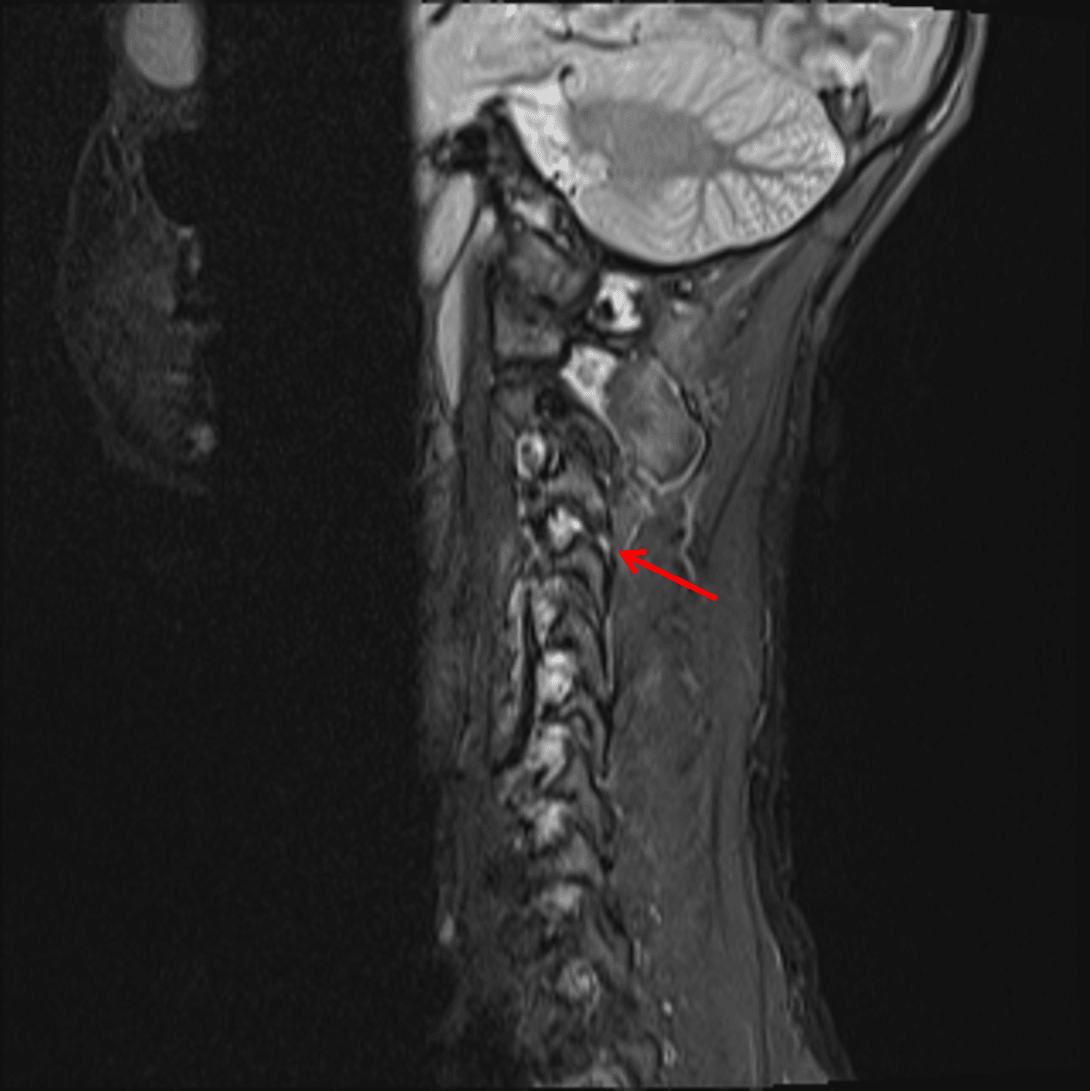

- Focal kyphosis with widening of the interspinous interval at C3-C4

- Perched right C3-C4 facet joint

- T2/STIR hyperintensity in the interspinous ligaments at multiple levels, most pronounced at C2-C3, C3-C4, and C5-C6, and in the supraspinous ligament at the levels of C2-C3 and C3-C4

- T2/STIR hyperintensity in the right C3-C4 facet joint

- Focal discontinuity of the ligamentum flavum at the level of C3-C4 and possibly at C5-C6

- Small posterior disc bulges at C3-C4 and C4-C5 result in partial effacement of the ventral CSF without significant spinal canal stenosis

Flexion distraction injury at C3-C4 with traumatic kyphosis, widening of the interspinous distance, and perched right C3-C4 facet. No marrow edema to suggest acute fracture, though CT should be considered for further evaluation given that only radiographs were obtained previously.

Findings concerning for focal disruption of the ligamentum flavum at C3-C4 and possibly at C5-C6, right C3-C4 facet capsular injury, multilevel interspinous ligament injury, most pronounced at C2-C3, C3-C4, and C5-C6, and supraspinous ligament injury at C2-C3 and C3-C4.

Likely traumatic disc bulges at C3-C4 and C4-C5, which partially efface the ventral CSF without significant spinal canal stenosis.

- Hyperflexion injuries result in narrowing of the anterior column and widening of the posterior column, as shown in this case with kyphotic deformity and widening of the interspinous distance at the involved level

Cervical Ligamentous Injury 1.2